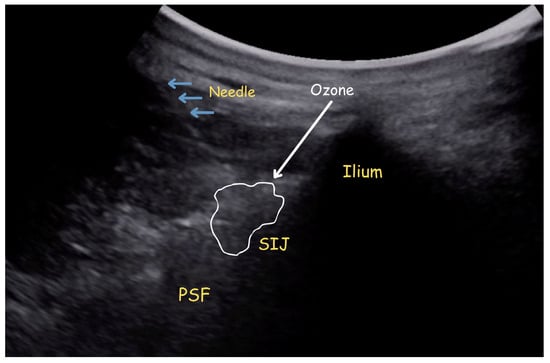

- For those of you in our rehab and pain medicine communities, a piece in Disability and Rehabilitation on ‘Ultrasound image guided injection of botulinum toxin for the management of spasticity: an implementation case study for practice recommendations and a governance framework’ (18 March)